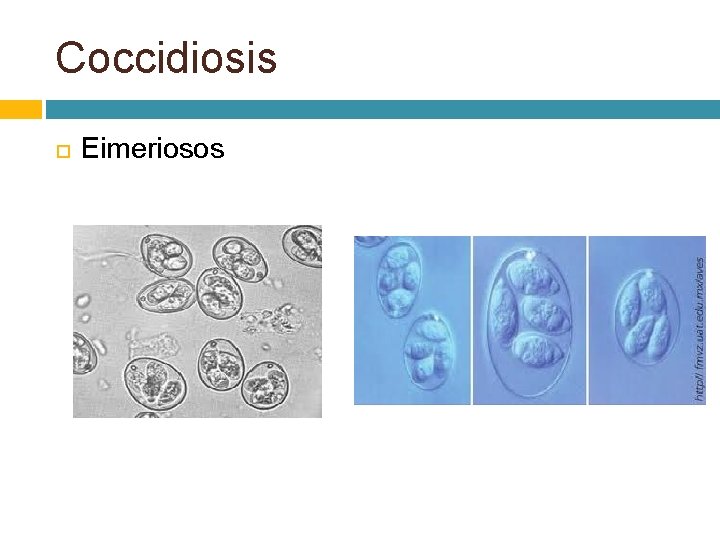

Coccidiosis Eimeriosos

Coccidiosis